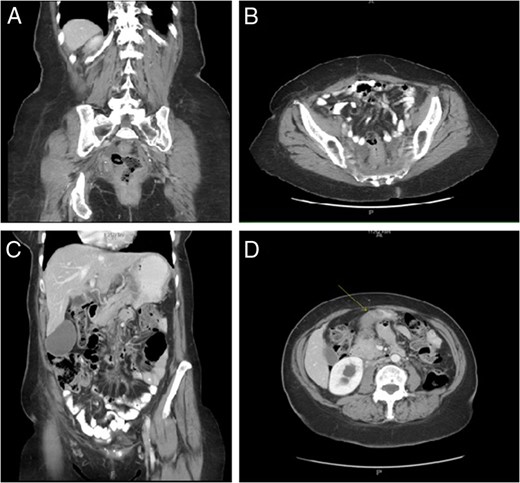

A 61-year-old African American female presented to her primary care provider with a 1-month history of nausea, emesis, constipation and 20 pound weight loss. She also reported superficial skin changes on bilateral breasts and a palpable mass in her left breast. Mammography revealed a hypoechoic lesion of the left breast and overlying asymmetry classified as BIRADS 4C which was not present on the patient's annual mammogram 8 months prior. The patient was referred to general surgery for biopsies of the left breast mass, overlying skin of both breasts and an axillary skin lesion. Pathology report of all lesions was ER(−), Her2/neu(−), GATA3(+) poorly differentiated mammary carcinoma. Computed Tomography (CT) scan of chest, abdomen and pelvis was performed for cancer staging. The scan revealed multiple osteoblastic metastasis within the sternum and spine, circumferential rectosigmoid mural thickening and duodenal bulb wall thickening (Fig. 1). The duodenal and rectal lesions were further evaluated with endoscopy. On upper endoscopy there was extrinsic compression of the antrum and stenosis of the pylorus and duodenal bulb. On colonoscopy, there was firm, friable, erythematous stricture circumferentially in the distal 5 cm of rectum (Fig. 2). Pathologic evaluation of the duodenal and rectal lesions revealed poorly differentiated carcinoma consistent with mammary primary (Fig. 3).

Circumferential rectosigmoid mural thickening (A, B); Duodenal bulb wall thickening (C, D).